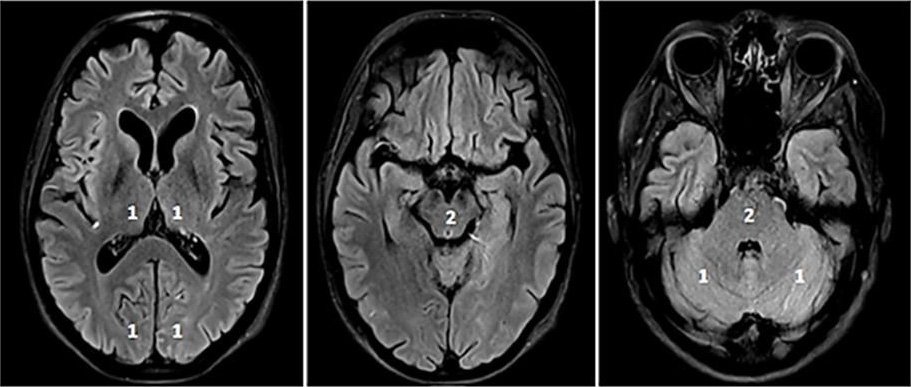

In posterior circulation stroke, MT is currently recommended in carefully

selected patients with BA occlusion [34, 35, 36]. Imaging tools such as the posterior

circulation collateral score (PC-CS) or posterior-circulation ASPECTS

(pc-ASPECTS; Fig. 3) might contribute to the decision-making process [42]. A

pc-ASPECTS

Fig. 3.pc-ASPECTS (posterior circulation ASPECTS). The pc-ASPECTS is a 10-point score evaluating the extent of ischemia in the posterior circulation. Scores of 10 points indicate no signs of ischemia in NCCT or MRI (diffusion weighted imaging, DWI). Each thalamus, occipital lobe and cerebellar hemisphere accounts for 1 point, and the mesencephalon and pons account for 2 points. Fig. 3 shows fluid attenuated inversion recovery (FLAIR) sequences because of better image quality.